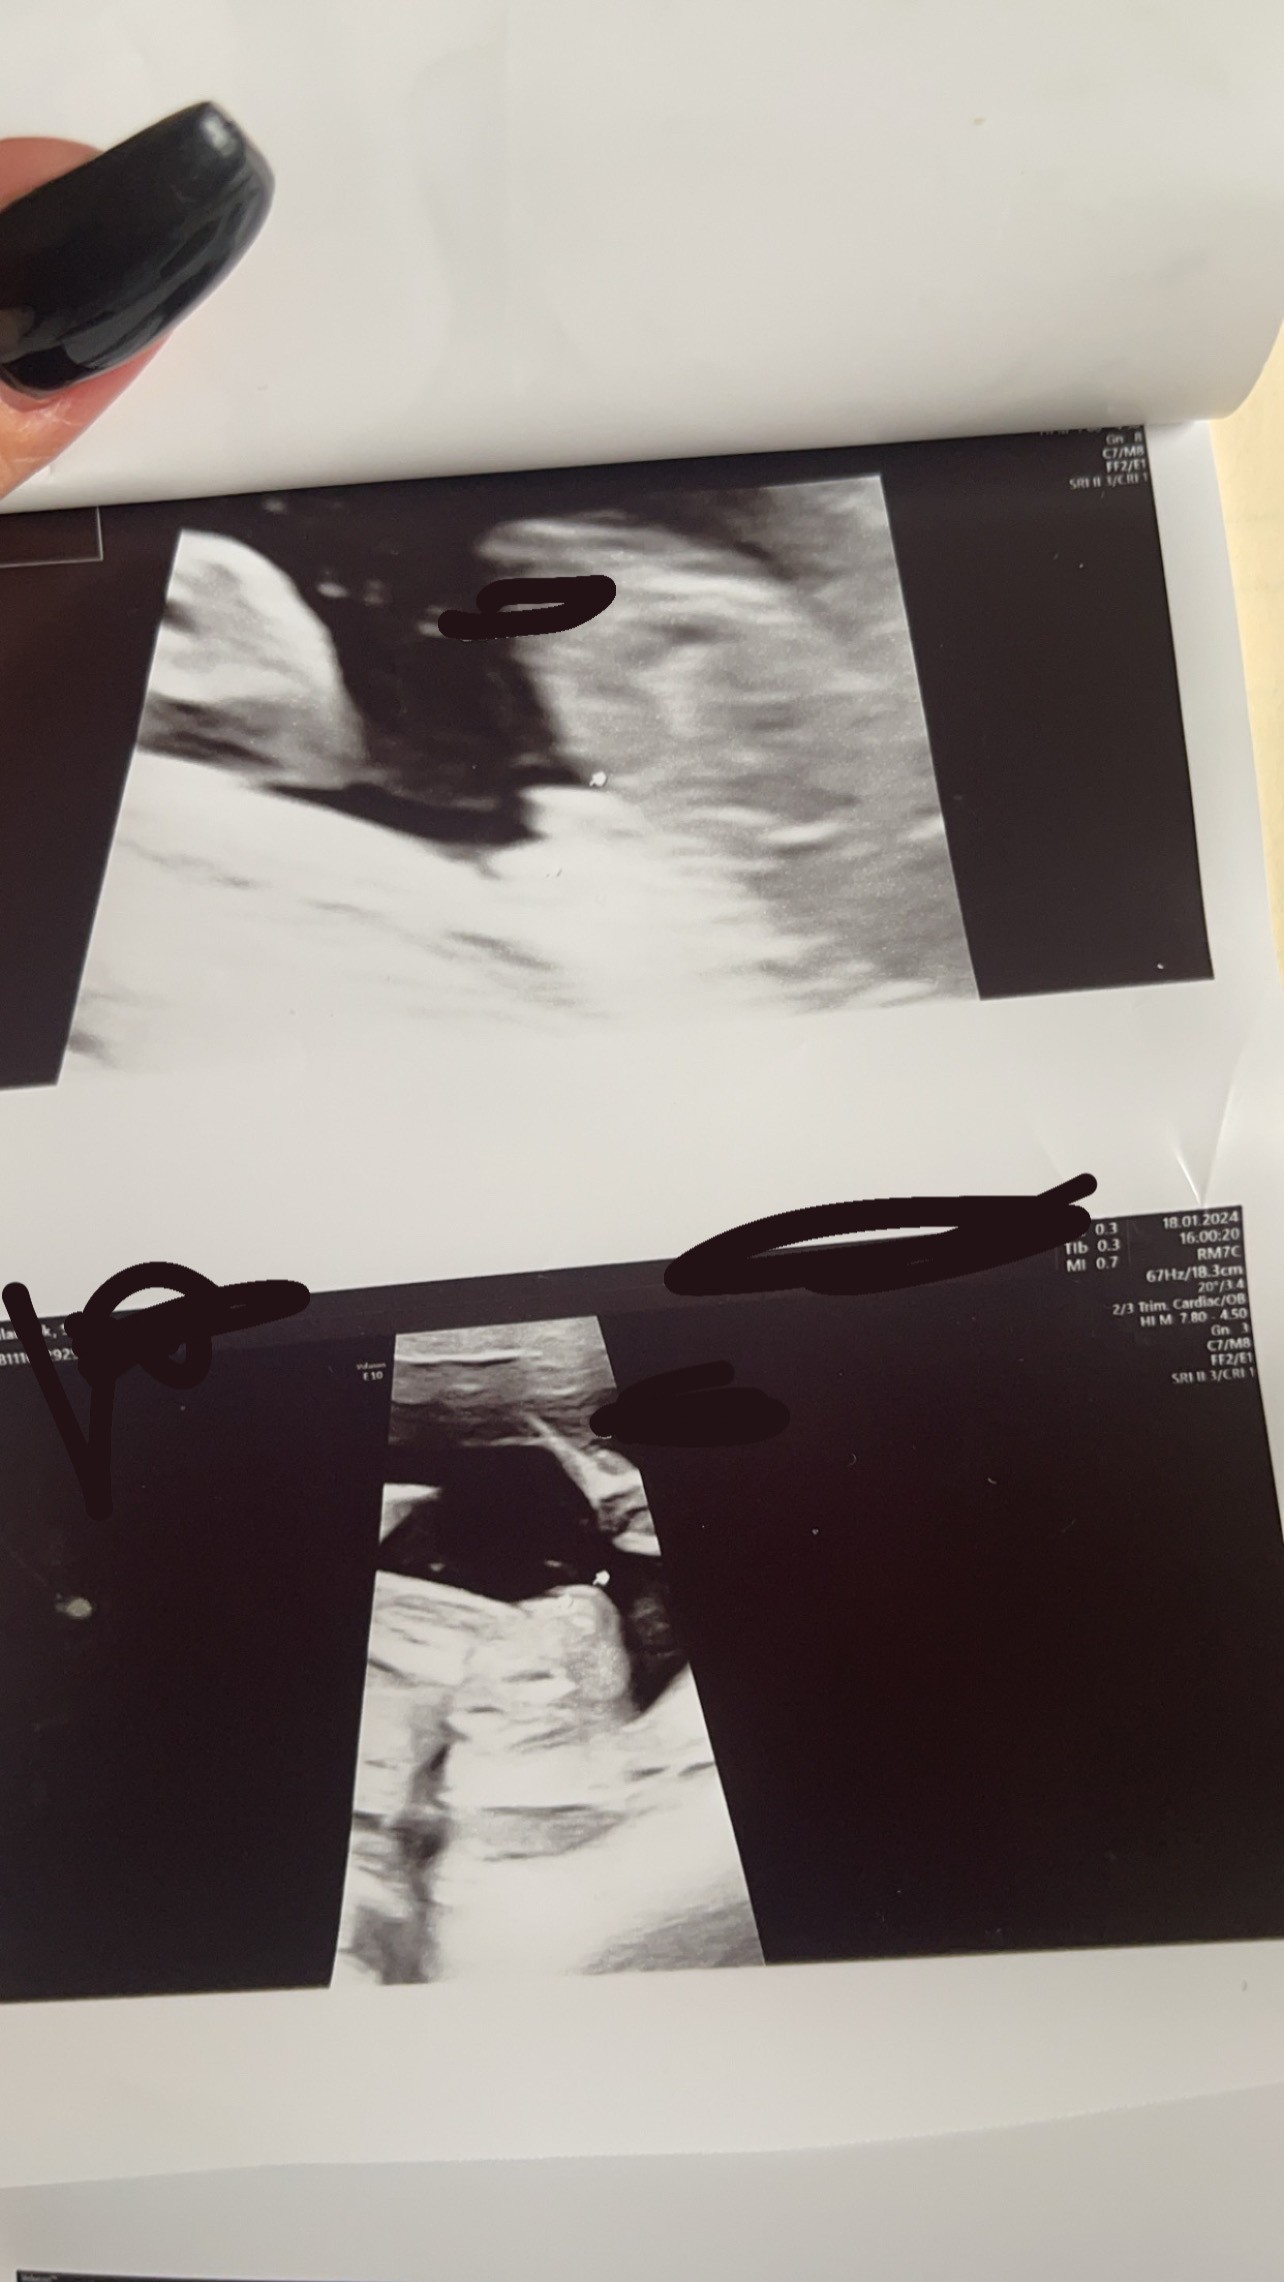

Jest to zdjęcie z badań połówkowych , lekarz mówi że dziewczynka , mój ginekolog też ale tyle się naczytałam pomyłek o płci że się wystraszyłam a połowa wyprawki już kupiona 😅 Może któraś z was miała córeczkę i podobnie wyglądało to na zdjęciach ? Jak uważajcie bo już panikuję

Strzałka jest zaznaczona płeć jak coś

Wygląda jak opuchnięte wargi sromowe. U mnie na połówkowych wyglądało to podobnie, jeśli to ujęcie od dołu nocnikowe. ale wiadomo są wyjątki, że po 20tc ujawnia się inna płeć :) Dobrze jest, gdy lekarz sprawdza jeszcze ułożenie narządów wewnętrznych, bo podobno na tym etapie to też się różni u chłopców i dziewczynek.